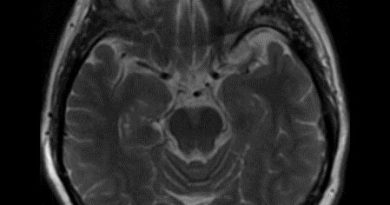

- B) Aksiyel T1A kontrastlı görüntüde kitle homojen yoğun kontrastlanmaktadır (ok). T2A görüntüde sinyal void vasküler yapılar içerdiği görülmektedir (ok).

- Spinal paragangliomalar T1 ağırlıklı görünülerde izo-hafif hipointens, T2 ağırlıklı görüntülerde ise izo-hiperintens görülürler.

- Kontrast madde enjeksiyonu sonrasında yoğun homojen kontrastlanma gösterirler.

- Lezyon içerisinde ve lezyon komşuluklarında flow-void genişlemiş vasküler yapılar bulunur.